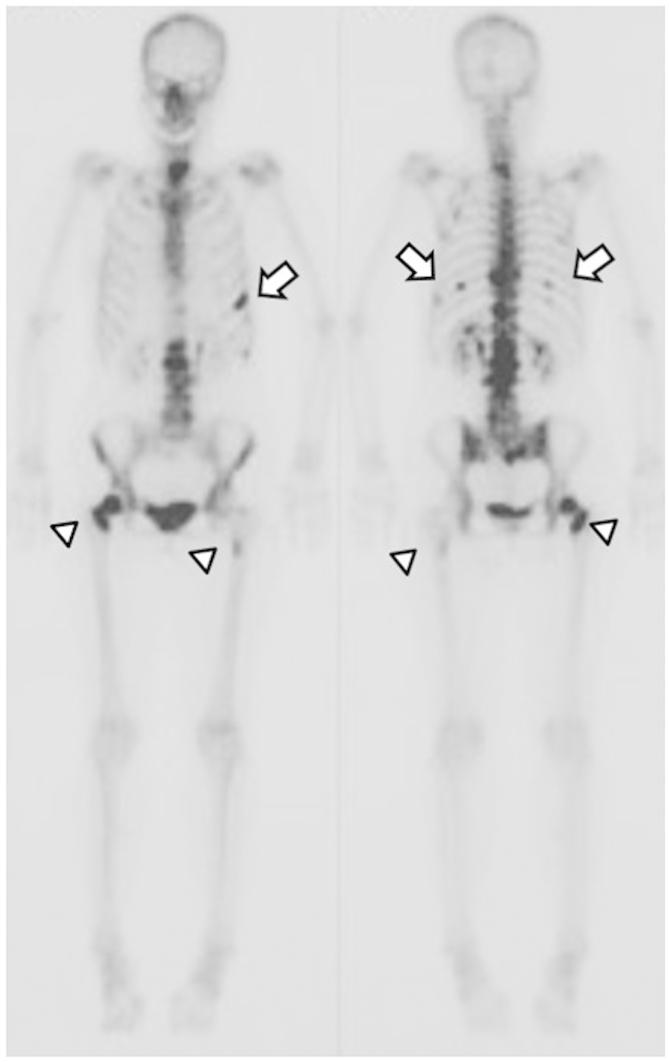

Cases of ossification and increased bone mineral density (BMD) at sites of bone metastasis following zoledronic acid (ZA) treatment have not been reported. The current study presents the case of a 65-year-old patient with lung adenocarcinoma and bone metastases in the lumbar vertebrae and femurs. Ossification and an increase in BMD at the metastatic sites was achieved following treatment with ZA and irradiation of the bone metastatic sites. The patient was able to maintain a normal lifestyle for over two years, despite the bone metastases. Therefore, as treatment with ZA was demonstrated to improve patient quality of life, physicians should consider this treatment strategy, particularly for the treatment of metastasis in weight-bearing bones.

唑来膦酸(ZA)治疗后骨转移部位出现骨化和骨矿物质密度(BMD)增加的病例尚未见报道。本研究报告了一例65岁肺腺癌患者,其腰椎和股骨发生骨转移。在使用ZA治疗并对骨转移部位进行放疗后,转移部位实现了骨化且BMD增加。尽管存在骨转移,该患者仍能够维持正常生活方式超过两年。因此,由于已证明ZA治疗可改善患者生活质量,医生应考虑这种治疗策略,尤其是用于治疗负重骨转移。